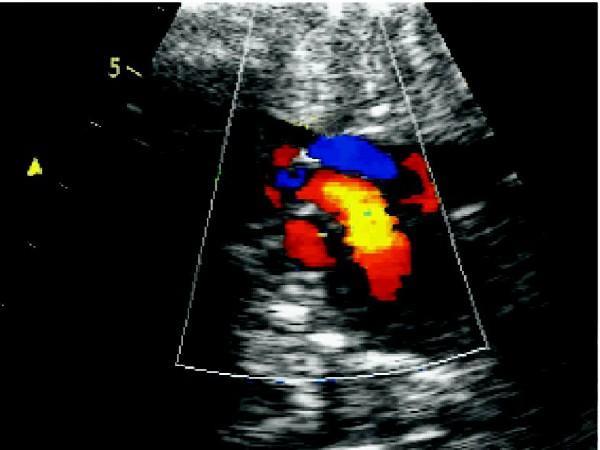

①二尖瓣和三尖瓣取胎儿四腔心切面,通过彩色多普勒观察二尖瓣及三尖瓣口正常纯蓝或纯红血流信号(取决于探头与心尖的方向)。频谱多普勒显示二、三尖瓣口的血流频谱,与正常人不同的是,胎儿二、三尖瓣口血流E峰<A峰。

③卵圆孔取胎儿四腔心切面,彩色多普勒显示卵圆孔处血流信号为房水平右向左分流。